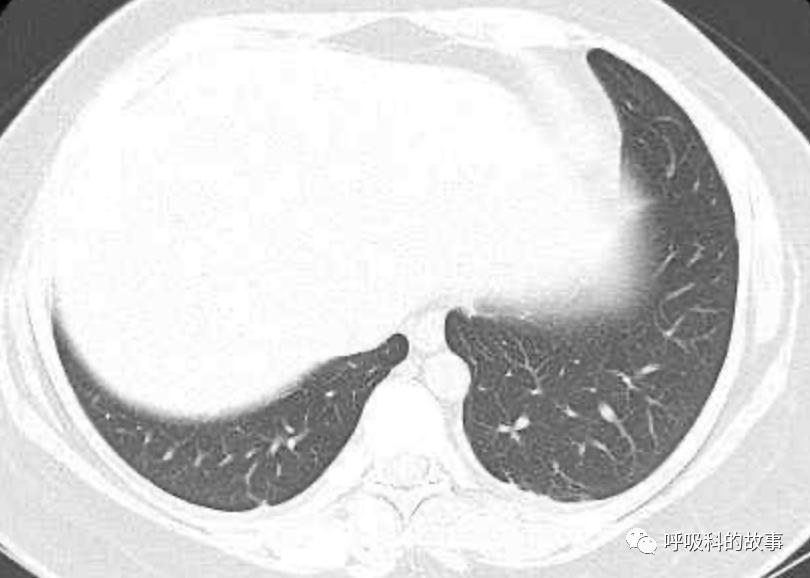

患者发热后行胸部CT检查(6月21日,住院第13天),可见两下肺有条片影,当时考虑是肺炎引起的发热。

可是在6月26日(往院第18天)仍持续发热的情况下复查肺部CT,肺部病灶已明显吸收了。那么患者发热的原因到底是什么呢?为什么患者高热的情况下血白细胞不升反降,C反应蛋白也没有明显增高?这个时候消化科医生也迷茫了,这可怎么办?于是请感染科和呼吸科医生一起会诊,共商计策。